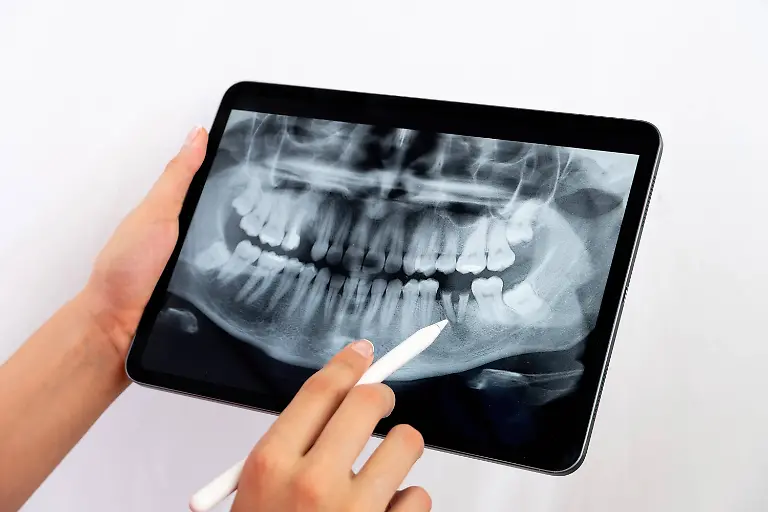

Er war ein Revolutionär der Medizintechnik: Der Physiker Wilhelm Conrad Röntgen entdeckte 1895 zufällig die X-Strahlen, was nicht nur für die Diagnostik in der Medizin ein Meilenstein war. Später wurden die Strahlen und das Verfahren nach ihm benannt. Röntgen starb vor 100 Jahren in München.